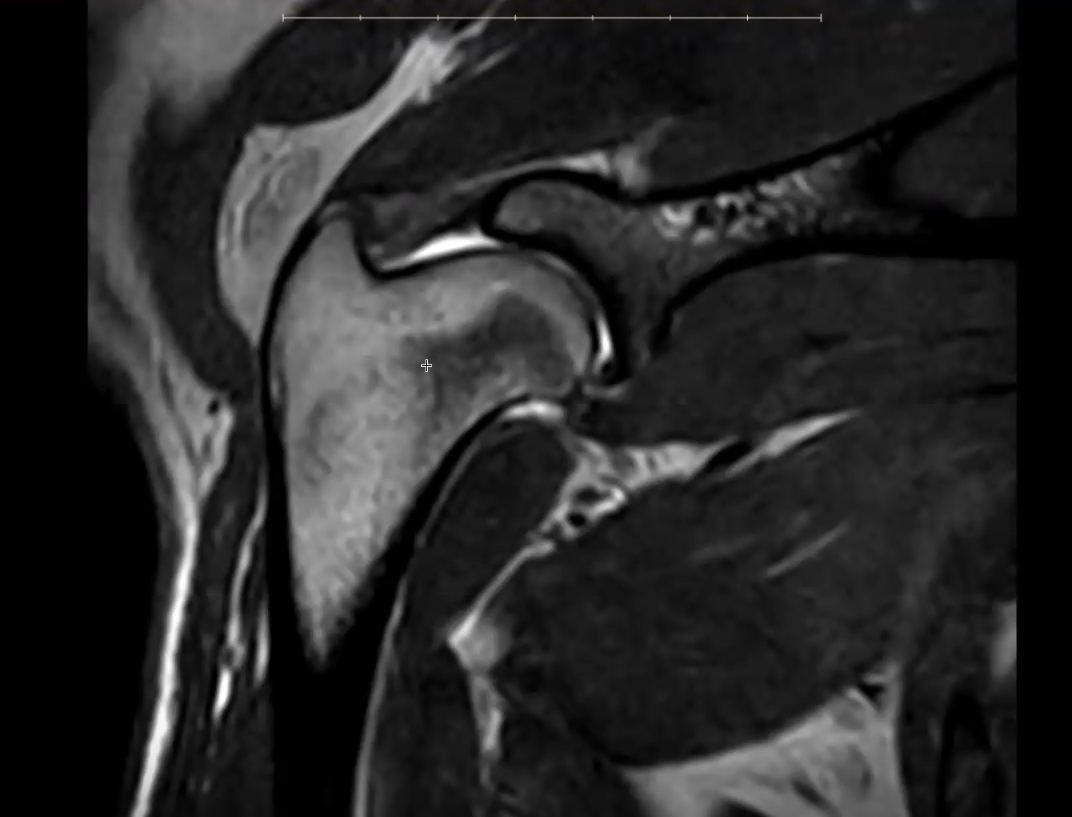

MRI scans of Kal's shoulders showing bilateral pathology. Findings include biceps tendinopathy with fluid in the bicipital tendon sheath (both sides), subscapularis tendon injury, and synovitis, with more advanced changes on the right.

Close-up MRI view of Kal's shoulder joint, showing the structures involved in his tendon and joint inflammation.

More pronounced abnormalities were identified in the right shoulder:

• Increased signal and structural changes within the subscapularis tendon, extending into the adjacent muscle

• Contrast enhancement within the joint, consistent with synovitis (joint inflammation)

• Intratendinous signal change in the biceps tendon

• Moderate fluid accumulation within the bicipital tendon sheath

Together, these findings indicate more advanced tendon injury and active joint inflammation.